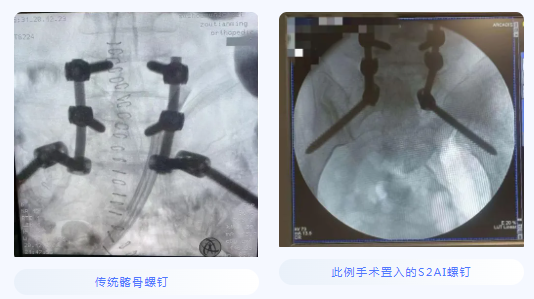

患者感染病灶位于腰5、骶1,骶1骨质破坏,置入椎弓根钉强度欠佳,容易松动、拔钉,导致内固定失败。传统使用髂骨螺钉替代骶1椎弓根钉,但髂骨螺钉存在钉尾突兀刺激皮肤、与近端腰椎椎弓根钉不在同一纵线、连接困难等缺点。鉴于脊柱微创外科团队过去已在美敦力S7系统辅助下成功完成多例精准导航脊柱外科手术,胡资兵教授团队在征得患者及家属同意后,决定采用“C臂导航下经后路腰5、骶1感染病灶清除、椎管减压、S2AI螺钉、腰椎椎弓根钉棒内固定术”来解决此难题。

S2AI为经骶2骶髂螺钉,置入后与近端腰椎椎弓根钉保持在同一纵线上,连接方便,而且不存在钉尾突兀刺激皮肤的问题,近年来已成为备受推崇的腰骶固定方式,但一直以来S2AI螺钉的置入都极具挑战性。此例患者软组织丰厚,腰骶段暴露困难,更加大了置钉难度。C臂导航对S2AI置入的准确度和安全性具有非常明显的优势,大大降低了以往仅仅根据术者经验完成手术的风险,实现了数字化、精准化的质的飞跃。在清晰的图像指引下,经过3小时的精细操作,成功为这位病情复杂的患者施行了手术。整个手术过程出血量少,S2AI螺钉置入精准,病灶清除彻底。术后患者顺利康复。